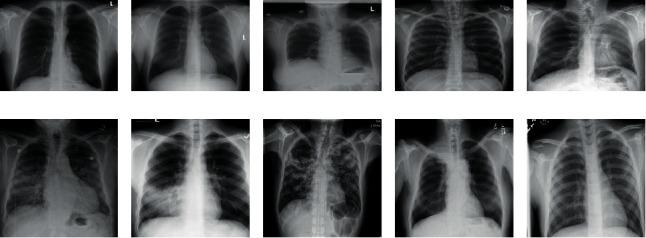

METHODS

We conducted a cross-sectional study in the Cape Coast Teaching Hospital in the Central Region of Ghana among 99 nonradiologists, comprising 10 doctors in residency programmes, 18 medical officers, 33 house officers, and 38 final year medical students. The data collection was done with a semistructured questionnaire in two phases. In phase 1, ten CXRs were presented without patient's clinical history. Phase 2 involved the same ten CXRs presented in the same order alongside the patient's clinical history. Participants were given 3 minutes to interpret each image. Median and interquartile ranges were used to describe continuous variables, while frequencies and percentages were used to describe categorical variables. Test of significant difference and association was conducted using a Wilcoxon rank-sum test/Kruskal-Wallis test and chi-square ( ) test, respectively.